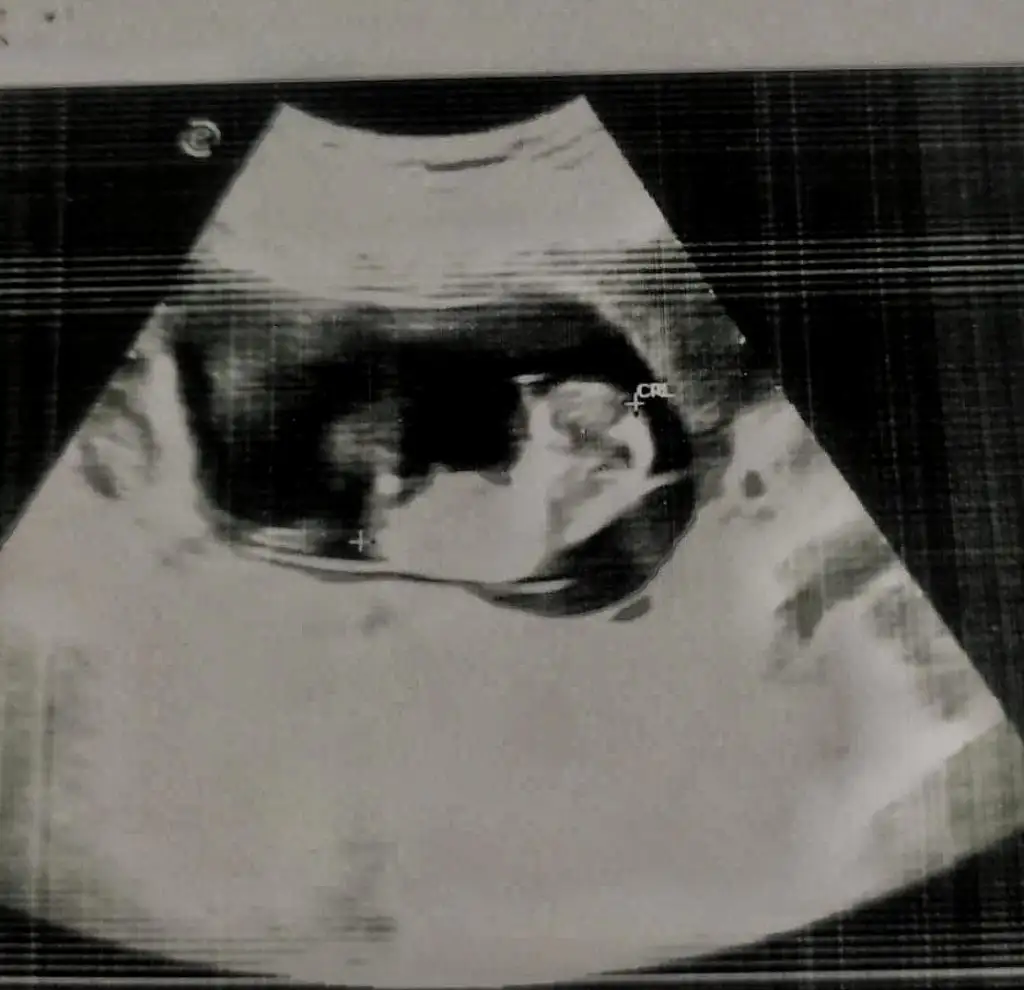

İnanamıyorum. 16+3’te bile belli olmayabiliyor demek ki.

Ben de tam o hafta için randevu aldım ki belli olsun öğreneyim diye. ama daha çok beklemem gerekebilir demek ki.

Bu da doğru değil bence. 14.haftada kız yorumu alıp 17de erkek denen bebek de çok mesela. Bazen cidden göstermeyebiliyor. Kaç tane örnek var böyle hep kız denmiş ama daha geç haftalarda erkek olduğu anlaşılan.

Zaten kiz yorumundan erkege donebiliyor bebek. Ama 12. Haftada erkek oldugu belli olan bebegin kiza donusu cok azdir. Benim genel olarak duyup gordugum erkek bebekler

Her zaman kendini daha erken belli ediyor. Gec gorunenlerde doktorla veya ultrasonla alakalidir.